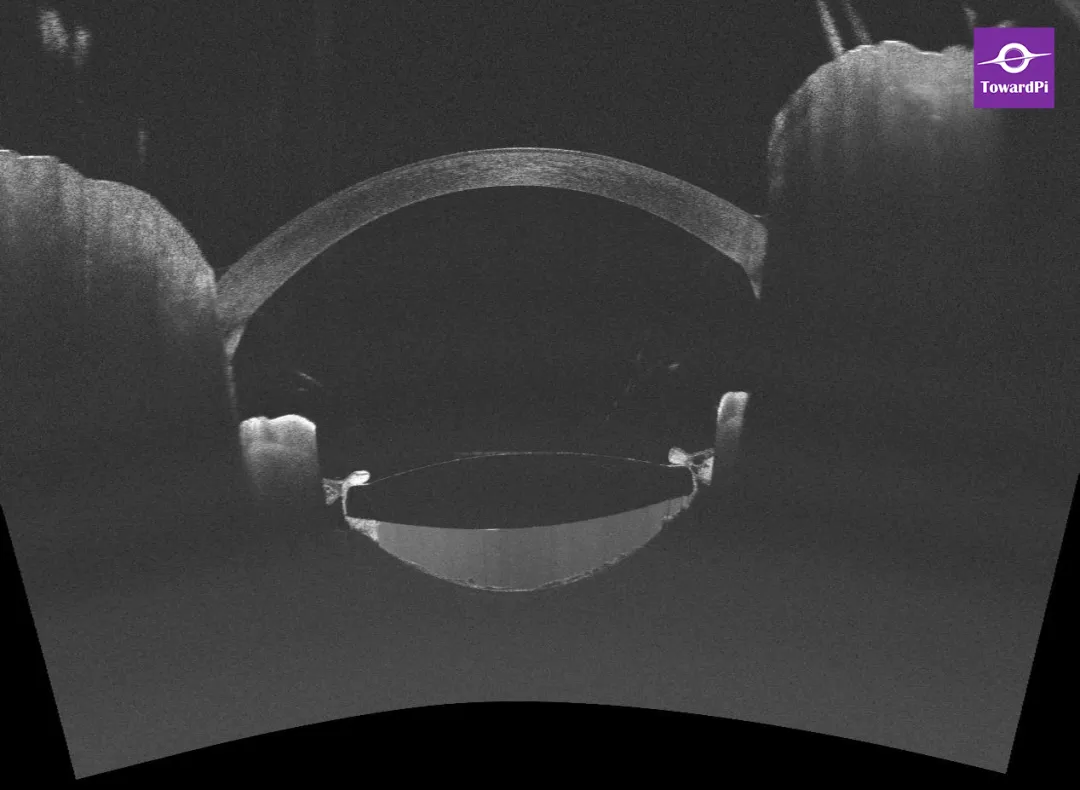

图1. IOL后表面与后囊膜之间存在间隙。

图3. 前节OCT:IOL后表面与后囊膜之间可见密集高反射信号(积液),囊袋膨胀扩张,后囊膜可见散在的囊样空腔(空泡)及点片状高反射信号(混浊)。